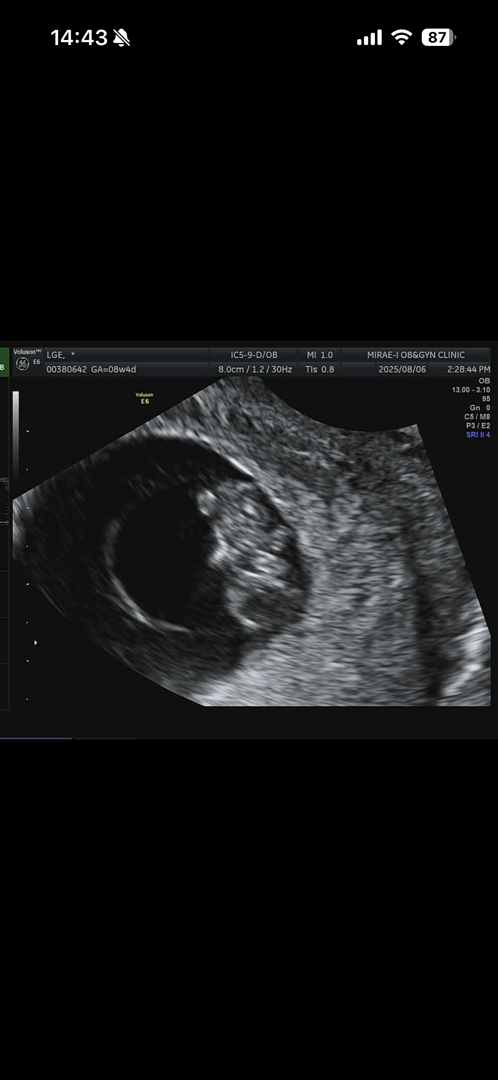

8주4일차 병원 다녀왔는데 아기는 8주5일 정도로 주수에 맞게 잘 크고 있다고 해요. 귀여운 곰돌이 모양 벌써 봤답니다. 토는 안하지만 하루종일 배멀미 입덧 때문에 입덧약도 처방 받아 왔어요.